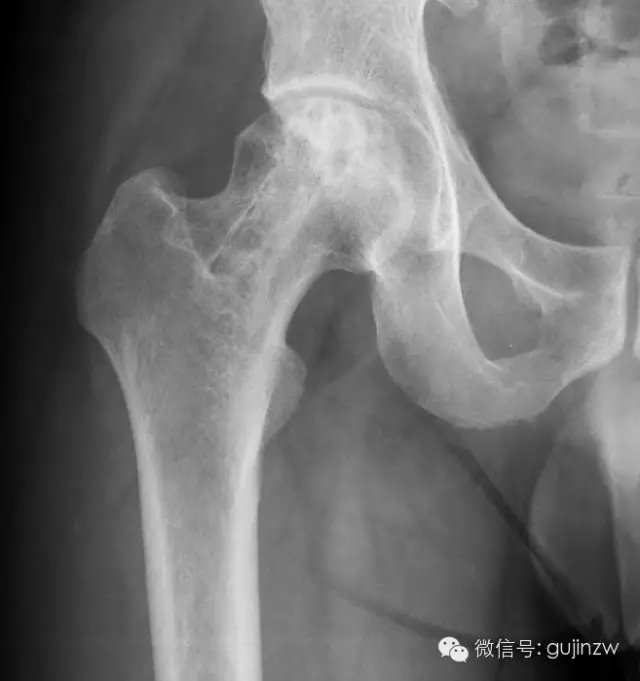

4、骨阻擋:髖關(guān)節(jié)脫位髖臼加蓋